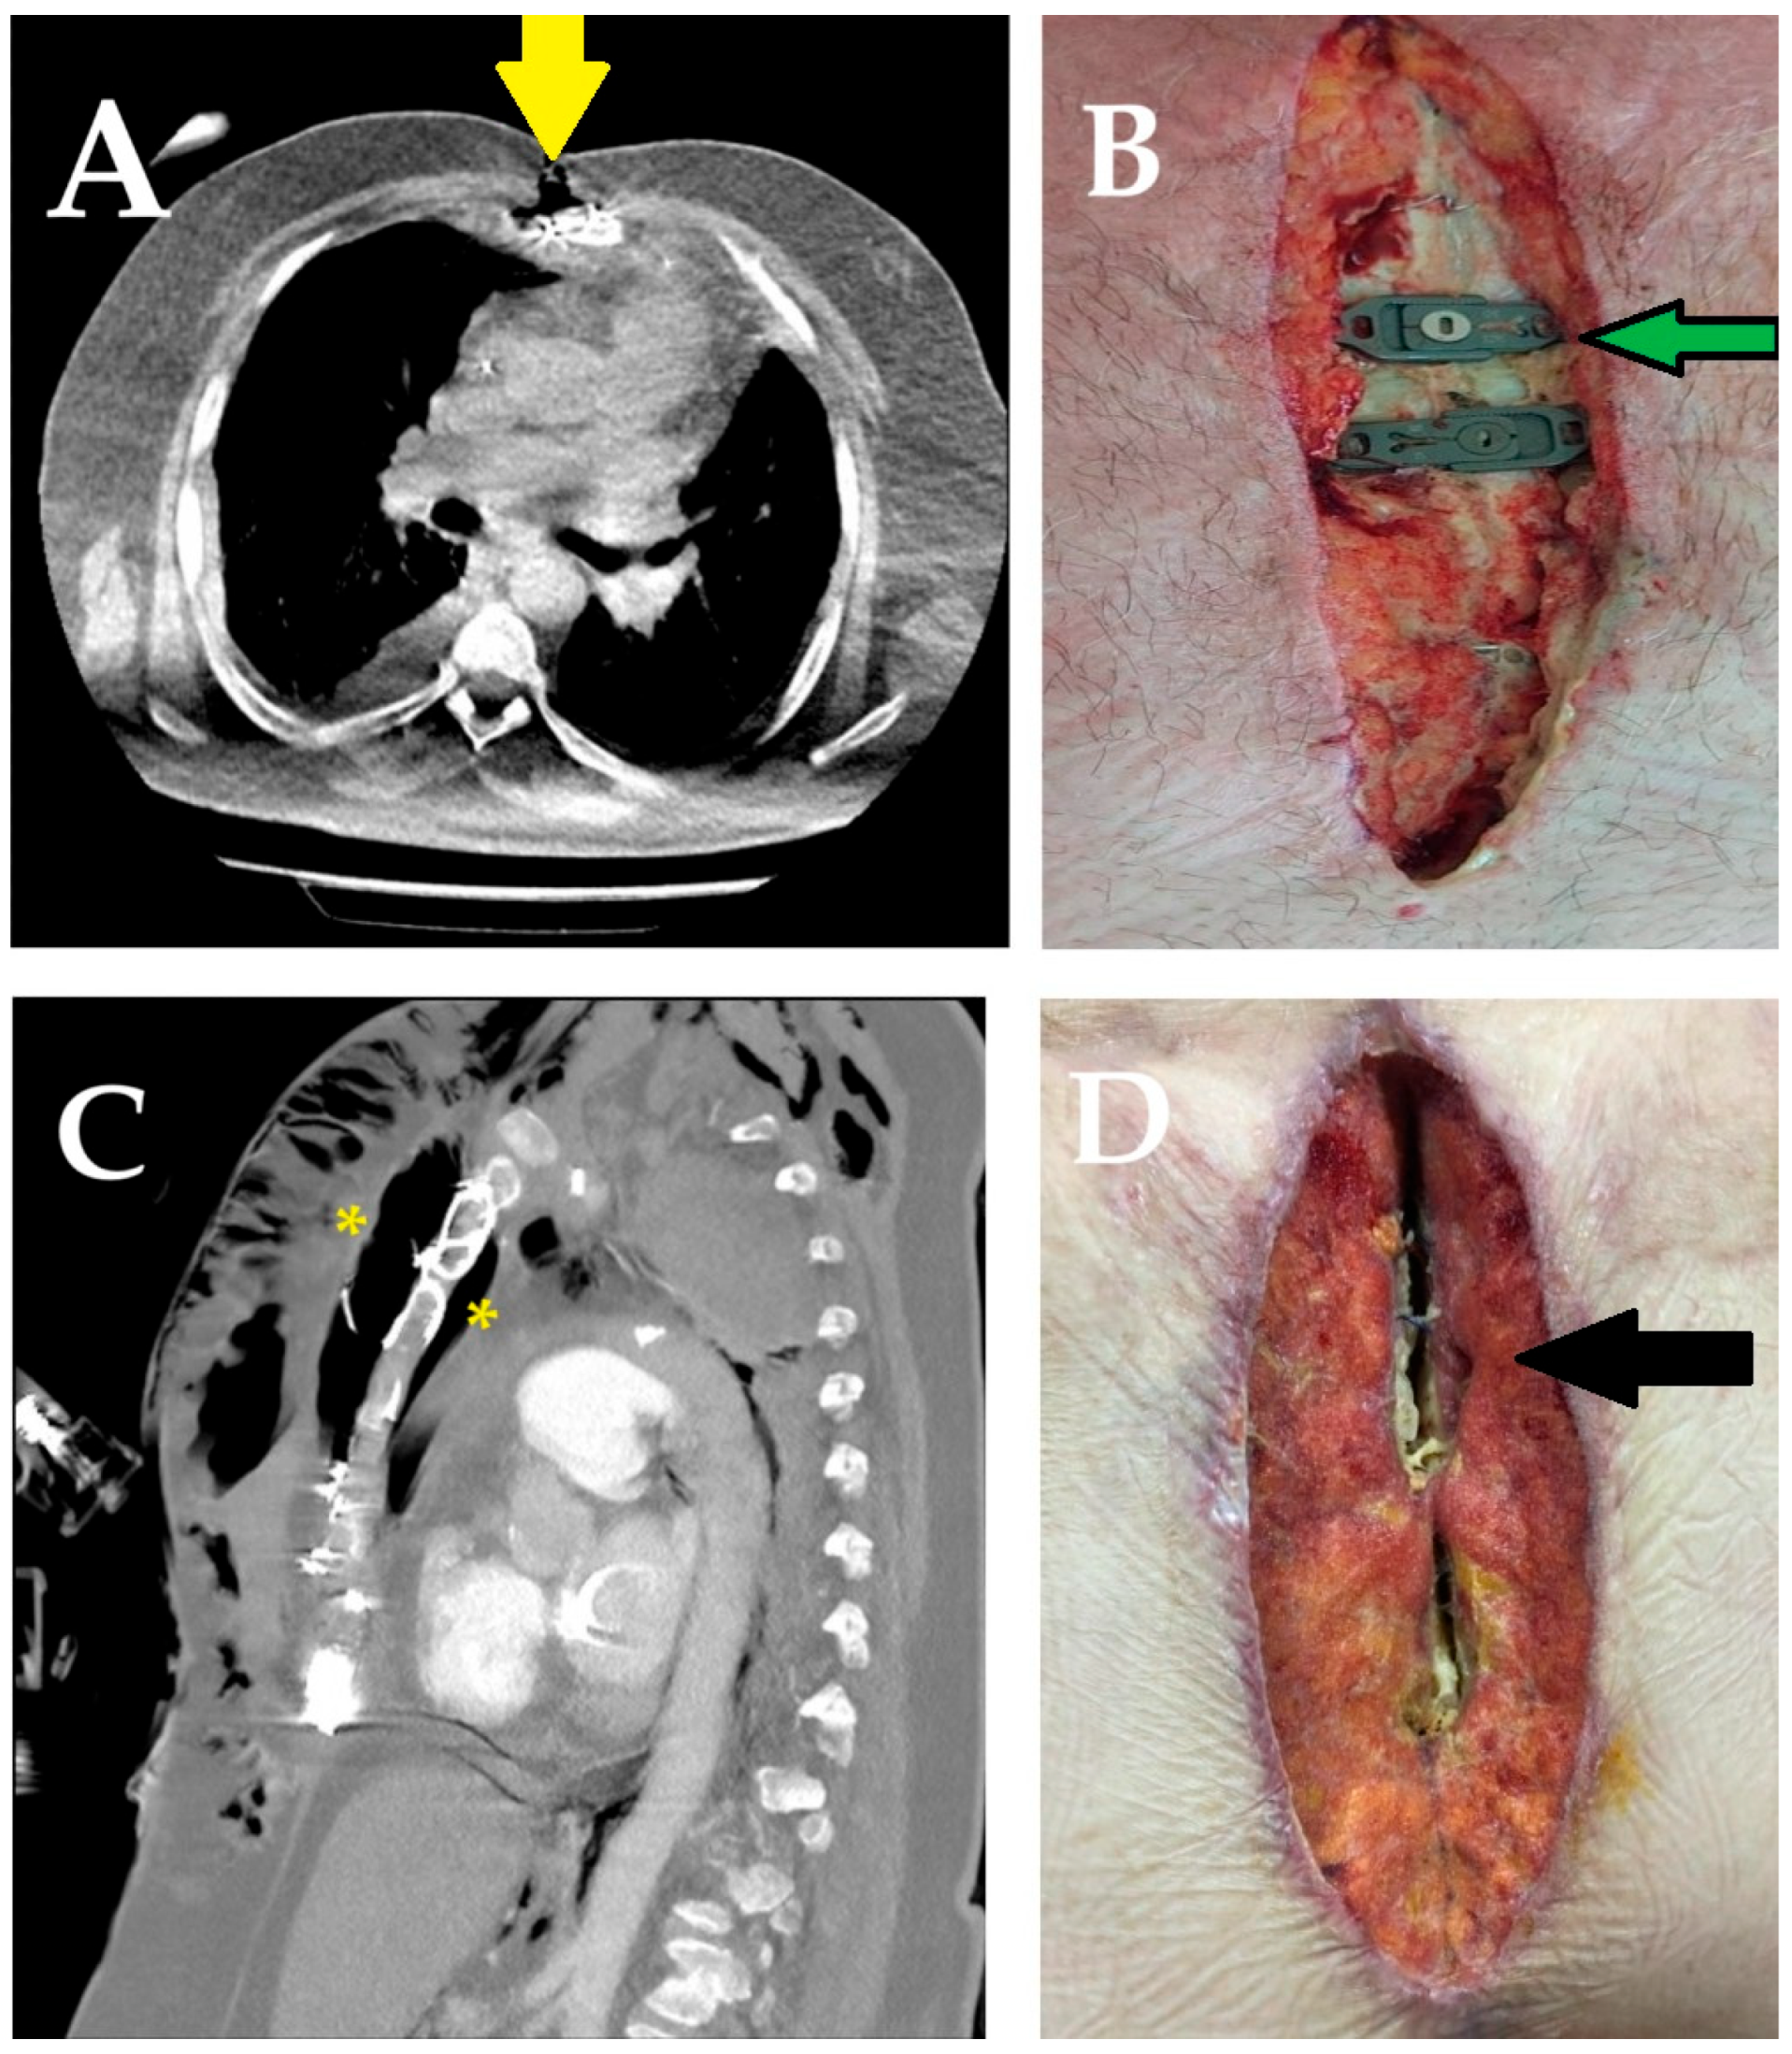

2.4. Surgical Technique